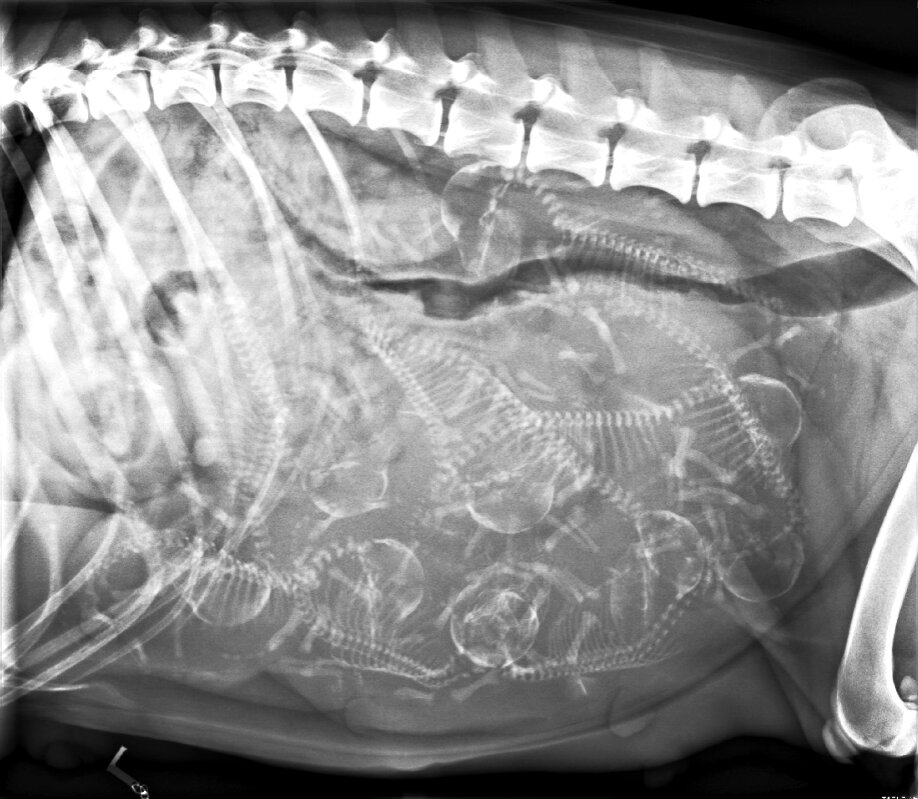

Heute waren wir mit Vita beim Trächtigkeits-Röntgen - wir sind beim Zählen auf 9 zu ewartende Welpen gekommen!